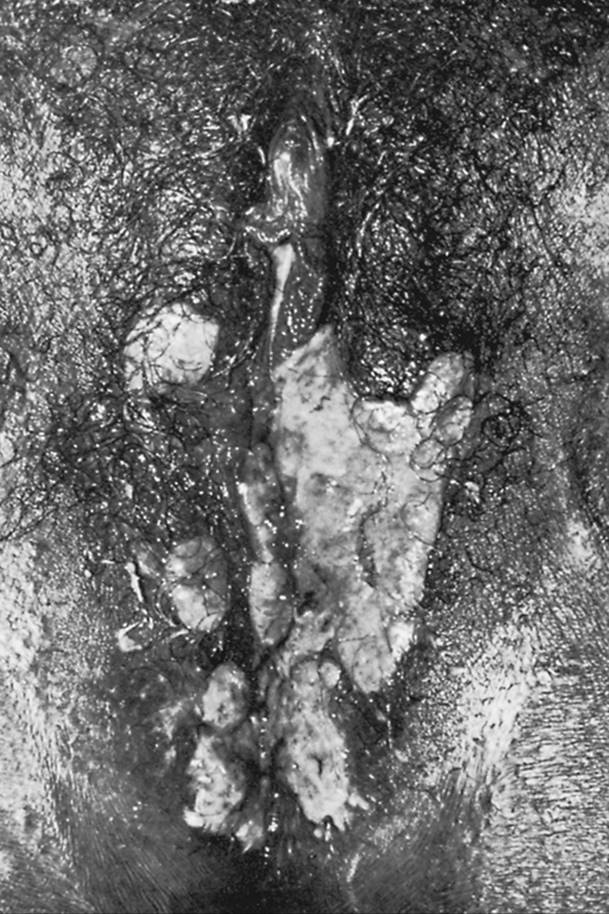

Genital human papillomaviruses (HPV) are DNA viruses that are distinct from papovaviruses that cause the common wart. HPV thrives in the moist genital area and usually is sexually transmitted. HPV infection is common and typically subclinical. HPV DNA is found in the genitalia in 30% to 45% of women by PCR DNA amplification. The vulva is positive for HPV DNA in more than 40%, and the cervix in over 30%. Only 1% of the women have visible warts, and only 9% have a history of genital warts. The average incubation period for visible warts is 3 months. Genital warts most commonly occur on the labia and posterior fourchette (Fig. 32.1). They originally appear as individual lesions, although large confluent growths can occur if neglected. Vaginal and cervical warts are even more common than labial warts, although most of these are flat lesions visible only by colposcopy. Over 30 HPV types infect the genital tract. Visible genital warts are usually caused by HPV types 6 and 11; 3% of college women had these types. The flat-wart variant is caused by HPV types 16, 18, 31, 33, and 35 (found in 22% of college women tested) and is visible only by colposcopy. A biopsy of flat or atypical-appearing cervical warts is required to exclude cervical neoplasia. Biopsies of warts also should be performed for pigmented, unresponsive, or fixed lesions, or in immunocompromised patients. HPV types 16, 18, 31, 33, and 35 are associated with high-grade cervical dysplasia and cervical cancer where the HPV DNA is integrated into the cancer cell. Women with flat warts should have frequent Pap smears. At present, routine typing of HPV is not recommended to aid PAP smear interpretation or predict cervical dysplasia.

FIG. 32.1. Condylomata acuminata of the vulva.

Vulvar warts must be differentiated from the less verrucous, flatter growths of syphilitic condyloma latum (Fig. 32.2) and from carcinoma in situ of the vulva; dark field examination or punch biopsies may be required to differentiate these lesions. Small to medium-sized verrucous lesions can usually be treated with patient-applied podofilox (Condylox), imiquimod (Aldara), or by providers (cryotherapy, podophyllin, or trichloroacetic acid). Intralesional interferon and laser surgery represent alternative regimens. Small amounts of podophyllin (0.25 mL) should be used to avoid severe burns. Podophyllin, imiquimod, and podofilox are contraindicated during pregnancy. Large amounts of podophyllin have produced coma in adults and fetal death in pregnancy. A biopsy should be done on atypical lesions before therapy is initiated because podophyllin causes bizarre histologic changes that persist for months. Cryotherapy, trichloroacetic acid, or laser ablation can be used on vaginal warts during pregnancy. Recurrence rates of 50% probably relate to the failure of these methods to kill the virus in adjacent untreated areas. Severe burns have occurred from the use of 5-fluorouracil (5-FU) to treat warts; as a result its use is not recommended. Large warts may not respond to surgical or laser removal alone but also may require regional interferon therapy. Examination of sexual partners is unnecessary because most are already infected.